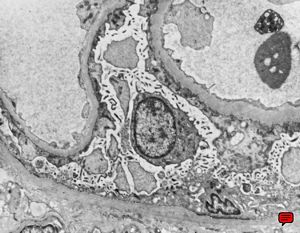

M,53y. | type III membranoproliferative glomerulonephritis